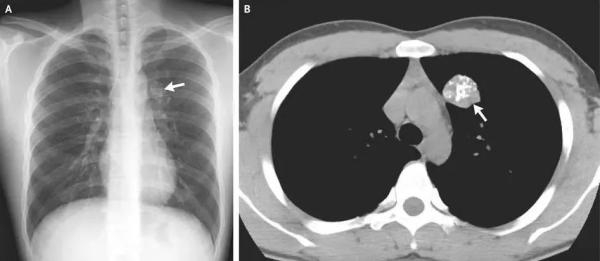

在甲状腺疾病中,恶性病变(如甲状腺癌)和良性病变(如结节性甲状腺肿)均可能存在钙化灶。甲状腺钙化大致可分为微钙化、粗大钙化和边缘环形钙化。

微钙化通常小于2毫米,表现为点状、针尖样、沙粒状钙化,在甲状腺乳头状癌患者中常见,但也并非有了这种钙化就是癌;粗大钙化表现为片状、弧形或其他不规则形钙化,通常发生在良性结节性甲状腺肿患者中;边缘环形钙化,一般出现在良性结节中。